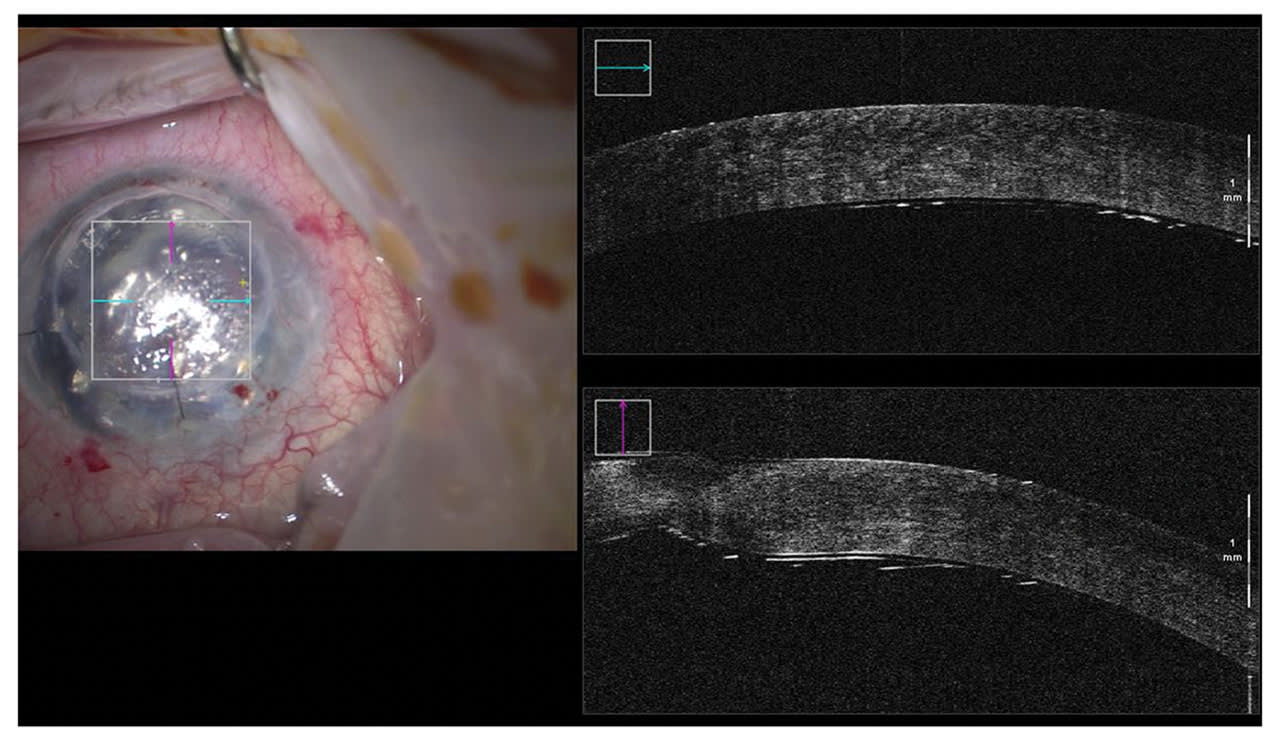

In comparison to using donor tissue, the manipulation of the implant is very simple. The graft can be handled directly with no fear of losing cells (Figure 1). Initially, the grafts had a tendency to detach requiring multiple rebubbles so the surgical technique was adapted to include a longer acting gas tamponade (C3F8) and a fixation suture (Figure 2). I strongly remind the patients not to rub their eyes. The suture can be removed a few weeks later at the slit lamp and this has significantly reduced the detachment rate. Postoperative steroids can also be reduced and stopped, unlike in endothelial keratoplasty.